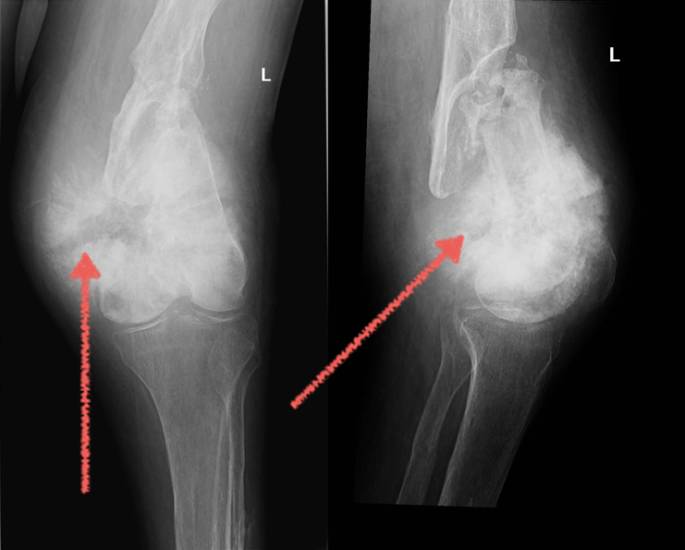

- Рентгеновское обследование является одним из самых эффективных методов диагностики. На снимке специалист, при наличии болезни, обнаруживает так называемый «треугольник Кодмэна», представляющий собой треугольный козырек. Кроме того обнаруживаются игольчатые спикулы;